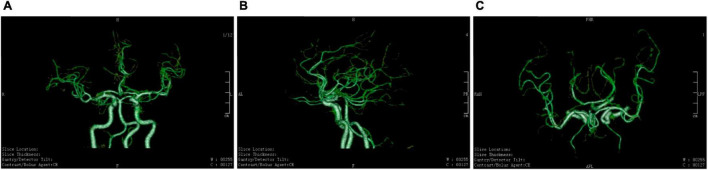

这项研究共有20名参与者,其中5名男性和15名女性,他们都有能力并熟悉独立倒立。除一名参与者外,所有参与者都有至少一年的瑜伽经验。年龄在10-59岁之间;中位年龄为43岁。在研究参与者中,17人在海拔2000米的地方进行了评估,其余人在海平面进行了评估。瑜伽倒立(sirsasana) 研究人员通过对颈~内动~脉的超~声检查来测~量~血~流。当参与者仰卧,然后倒立,然后再次仰卧时,测量...

今天和大家分享一篇关于瑜伽倒立练习的文章。关于各种瑜伽练习在生理上的影响,有很多观点围绕着这些练习。瑜伽倒立练习 其中一些源于对描述实践的经典梵文文献的解释。其他信息多来自于近年的一些研究来源产生的,在瑜伽界...在这项研究中,作者验证了 大脑血流量的自动调节,即身体将大脑血流量保持在一定健康值内的方法,在我们倒立时,只要我们在其他方面健康,大脑血流量

许多瑜伽习练者认为,头倒立(sirshasana)会增加大脑血流量,但这与脑血流量自动调节稳定的机制并不相符,俄罗斯圣彼得堡国立大学的研究团队希望通过对流经颈内动脉(Internal Carotid Artery,ICA)进入大脑的血流量进行检测,探讨头倒立对脑血流量的影响。研究样本 样本数量为20(5男15女),年龄在10岁到50岁之间(年龄中位...

研究结果明确显示:与我们常听到的解释相异,头倒立并不会增加大脑血液供应;相反,倒立期间,流经颈内动脉血流量会在脑血流自动调节机制下,出现一定程度的下降。另外,在 ...

1. 一项针对20名有经验的瑜伽练习者的研究发现,在头倒立期间,其中17名健康参与者的颈内动脉血流量并未增加,反而略有下降。研究者认为这是脑血流自动调节机制正常工作的结果。

1. 原文摘录:研究结果明确显示:与我们常听到的解释相异,头倒立并不会增加大脑血液供应;相反,倒立期间,流经颈内动脉血流量会在脑血流自动调节机制下,出现一定程度的下降。……20位受试者中的17位,在倒立期间并没有出现颈内动脉血流量增加的情况,流经左颈内动脉的血流量先是在倒立时减少,而在体式效应过后,血流量又恢复到基本水平。

Conclusions: Contrary to popular belief, Sirshasana does not increase blood flow to the brain through the ICA, but results in predictable reduction in cerebral ...

2. 美国国立卫生研究院(NIH)收录的一项于2019年发表在《替代与补充医学杂志》的研究,通过超声波测量了20名倒立练习者颈内动脉的血流。结果显示,绝大多数健康受试者在头倒立时,流向大脑的血流量并未增加,反而出现了符合自动调节机制的“可预见的减少”。

1. 原文摘录:Contrary to popular belief, Sirshasana does not increase blood flow to the brain through the ICA, but results in predictable reduction in cerebral blood delivery in compliance with known mechanisms of autoregulation of cerebral blood flow.

链接:https://pubmed.ncbi.nlm.nih.gov/31219304/

信源名称:美国国立卫生研究院 PubMed (Headstand (Sirshasana) Does Not Increase the Blood Flow to the Brain)

信源发布时间:2019-08-01

2. 原文摘录:研究结果明确显示:与我们常听到的解释相异,头倒立并不会增加大脑血液供应;相反,倒立期间,流经颈内动脉血流量会在脑血流自动调节机制下,出现一定程度的下降。

链接:https://m.toutiao.com/article/6850646721198817805/

信源名称:今日头条(编译自《替代和补充医学杂志》2019年研究)